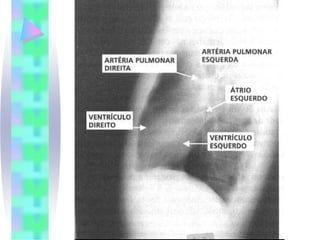

Radiologia

• Problemas que podem ser sugeridos ou

diagnosticados pelo RX de tórax

•   ICC

•   Edema Pulmonar

•   Derrame Pleural

•   Hipertensão Pulmonar Severa

•   Malformações Congênitas

•   Shunt esquerda-direita

•   Doença Cardíaca Valvar

•   Pericardite construtiva calcificada

•   Grandes Derrames Pericárdicos

•   Cisto pericárdico

•   Miocardiopatia

•   Sobrecarga das câmaras cardíacas

Radiologia • Problemas quepodem ser sugeridos ou diagnosticados pelo RX de tórax • ICC • Edema Pulmonar • Derrame Pleural • Hipertensão Pulmonar Severa • Malformações Congênitas • Shunt esquerda-direita • Doença Cardíaca Valvar • Pericardite construtiva calcificada • Grandes Derrames Pericárdicos • Cisto pericárdico • Miocardiopatia • Sobrecarga das câmaras cardíacas